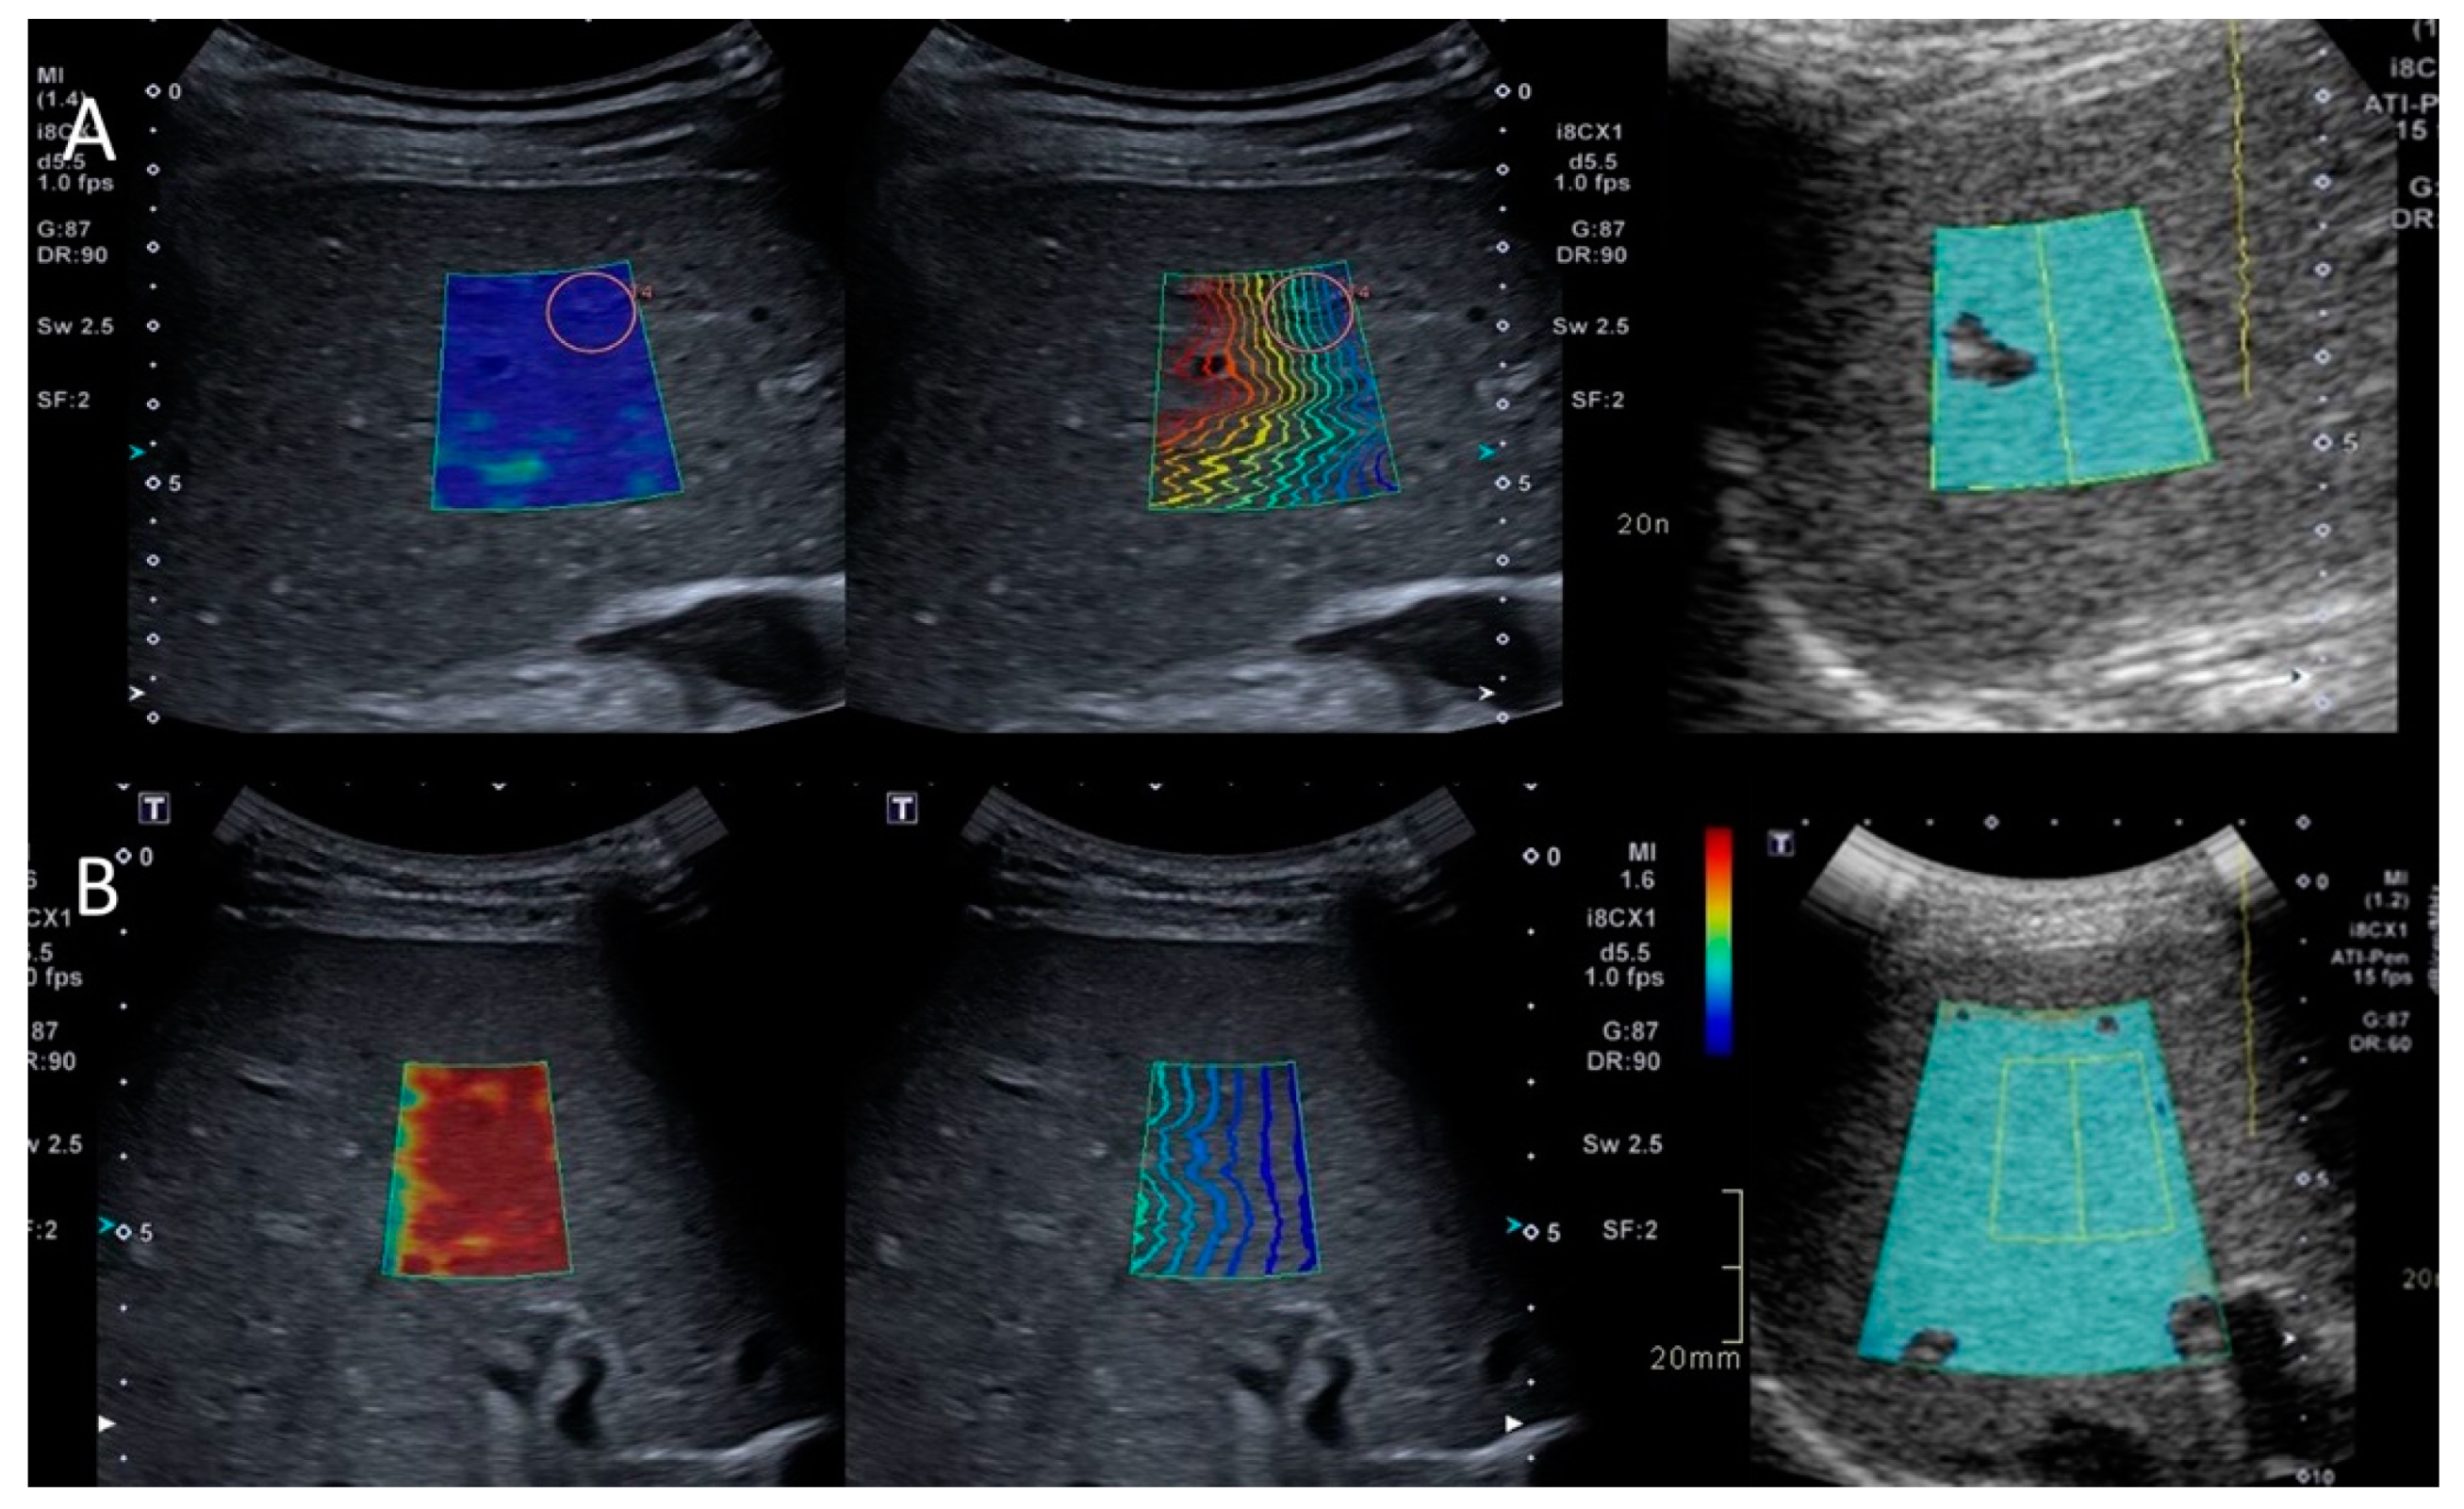

3.2.1. SWE

3.2.2. SWD

3.2.3. ATI